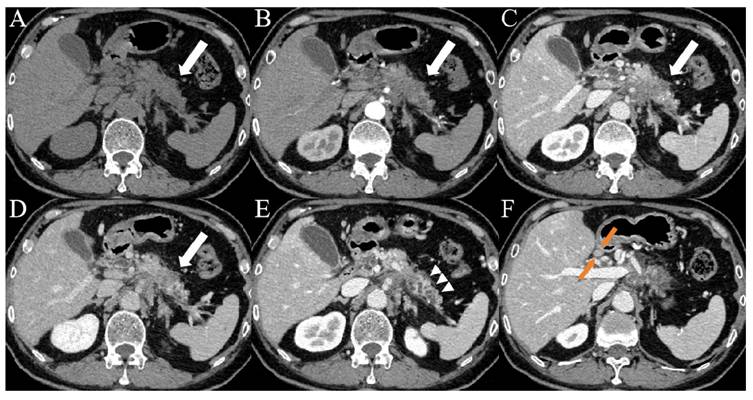

Figure 3

Images from a patient with PDAC. (A-D) CT images showed patchy areas of low density within the body of the pancreas (white arrows) with a hypovascular pattern, the margin of which was ill-defined. (E) Contrast-enhanced CT images during the portal venous phase showed duct dilatation and marked tail atrophy (arrowheads). (F) CT imaging showed a significantly enlarged lymph node (orange arrows) in the hepatogastric space, with a short axis measuring approximately 1.1 cm. The patient's CA19-9 level was 78.3 U/mL (> 37 U/mL), and the D-dimer level was 14.7 mg/L (> 0.84 mg/L).